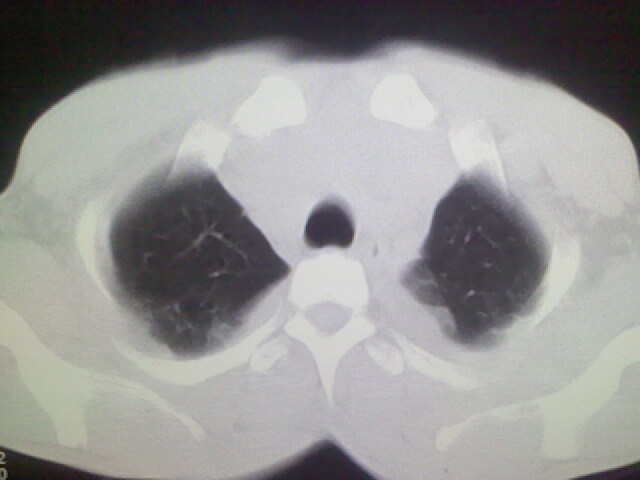

以下是引用杀毒软件在2008-9-3 6:11:00的发言:[br]侵袭性胸腺瘤------一般不侵到气管旁[br][br]考虑----纵隔淋巴瘤,心包及胸膜受累

以下是引用随光逐影在2008-9-3 7:07:00的发言:[br]1)考虑淋巴瘤可能。2)双侧胸腔积液(以左侧为甚)。3)心包积液。